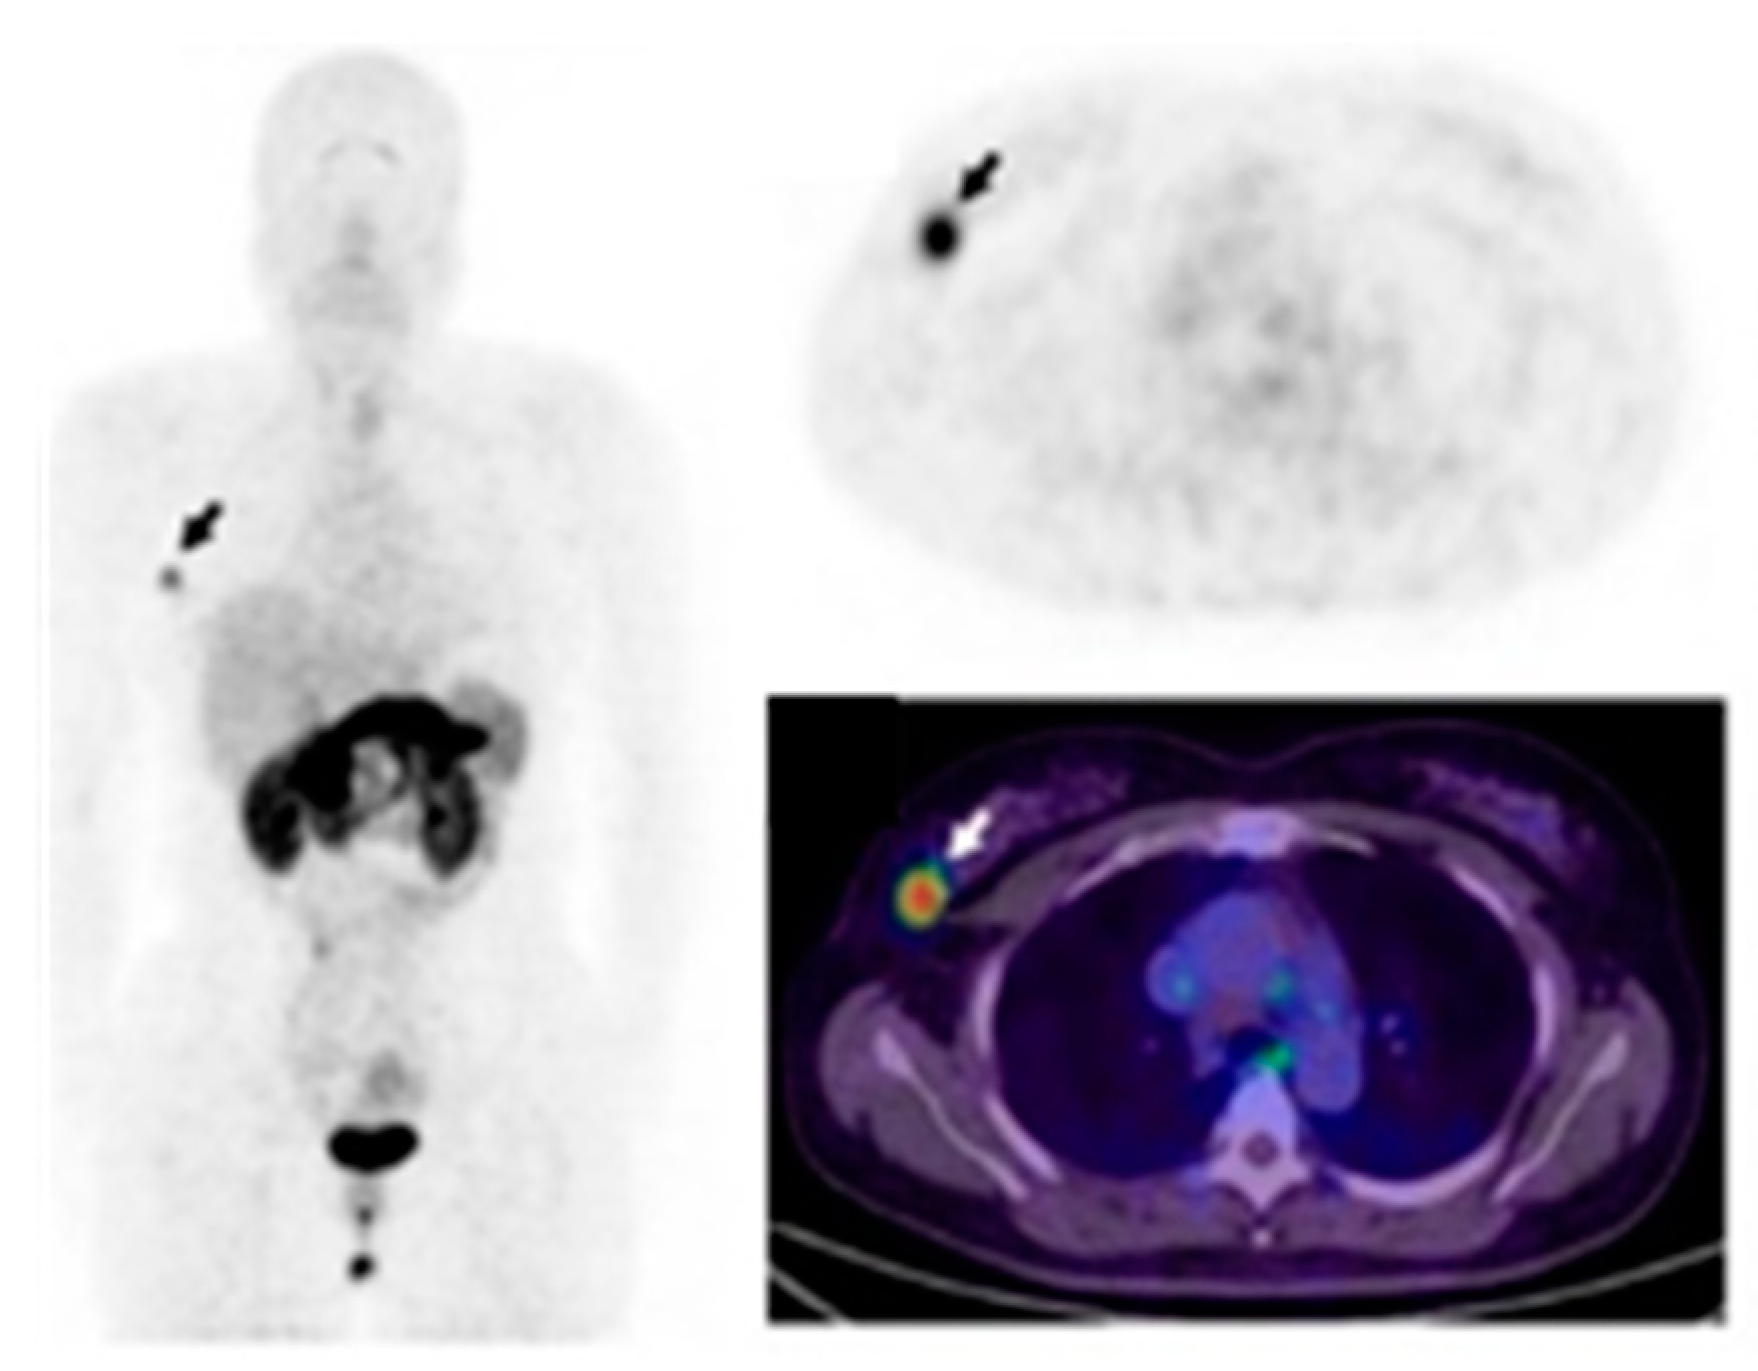

- Ulaner, G.A.; Hyman, D.M.; Lyashchenko, S.K.; Lewis, J.S.; Carrasquillo, J.A. 89Zr-Trastuzumab PET/CT for Detection of Human Epidermal Growth Factor Receptor 2-Positive Metastases in Patients With Human Epidermal Growth Factor Receptor 2-Negative Primary Breast Cancer. Clin. Nucl. Med. 2017, 42, 912–917. [Google Scholar] [CrossRef]

- Bensch, F.; Brouwers, A.H.; Lub-de Hooge, M.N.; de Jong, J.R.; van der Vegt, B.; Sleijfer, S.; de Vries, E.G.E.; Schröder, C.P. 89Zr-trastuzumab PET supports clinical decision making in breast cancer patients, when HER2 status cannot be determined by standard work up. Eur. J. Nucl. Med. Mol. Imaging 2018, 45, 2300–2306. [Google Scholar] [CrossRef]